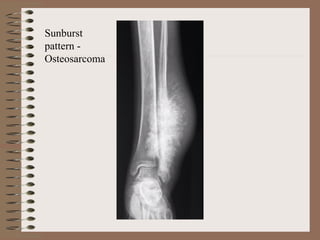

X ray – The tumour elevates the perostium to

surface of the involved bone . Sunburst pattern

due to osteogenesis within the tumour may also

occur

Sunburst

pattern -

Osteosarcoma

X ray –The tumour elevates the perostium to form cod man triangle formed by the angle between the elevated periosteum and the surface of the involved bone . Sunburst pattern due to osteogenesis within the tumour may also occur Parosteal (Juxta cortical ) osteosarcoma arise from the external surface of the bone ( parosteal or juxta cortical means outer to the cortex ) This has better prognosis